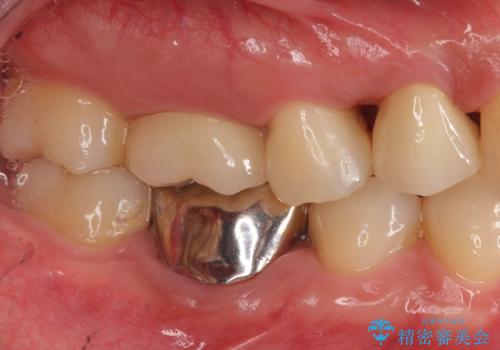

- 上の歯が大きく欠けたとのことで来院されました。

検査の結果、虫歯が大きくなりすぎたせいで薄くなった歯が欠けてしまった経緯が考えられました。

レントゲン画像上で歯茎の深いところまで虫歯になっており、保険治療では抜歯適応になってしまいます。

今回は虫歯の深いところが歯茎のラインにくるまで部分矯正で引っ張り出し、適合の良いかぶせ物を装着しました。

初診時の状態では虫歯が大きすぎて取り切ることができなかったため、まず歯を骨から引きあげて虫歯がしっかり除去できる状態にしました。

虫歯を取り切った後は、歯を引きあげたことで一緒に上がってきてしまった骨をならしていきます。

その後ラバーダムをして根っこの治療をし、被せ物を被せて治療終了となりました。